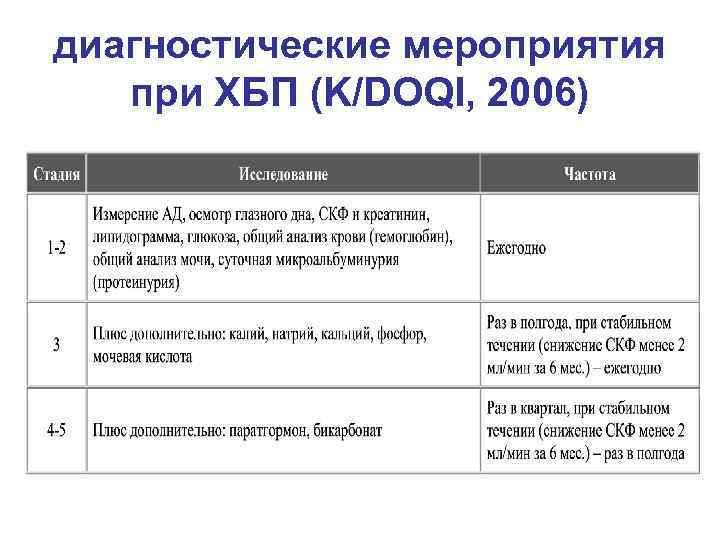

диагностические мероприятия при ХБП (K/DOQI, 2006)

диагностические мероприятия при ХБП (K/DOQI, 2006)